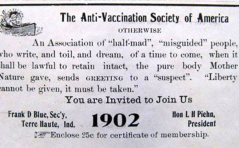

Covid 19

Covid-Trivia Impfgegnerschaft: ein alter Hut PDF DokumentIn und out